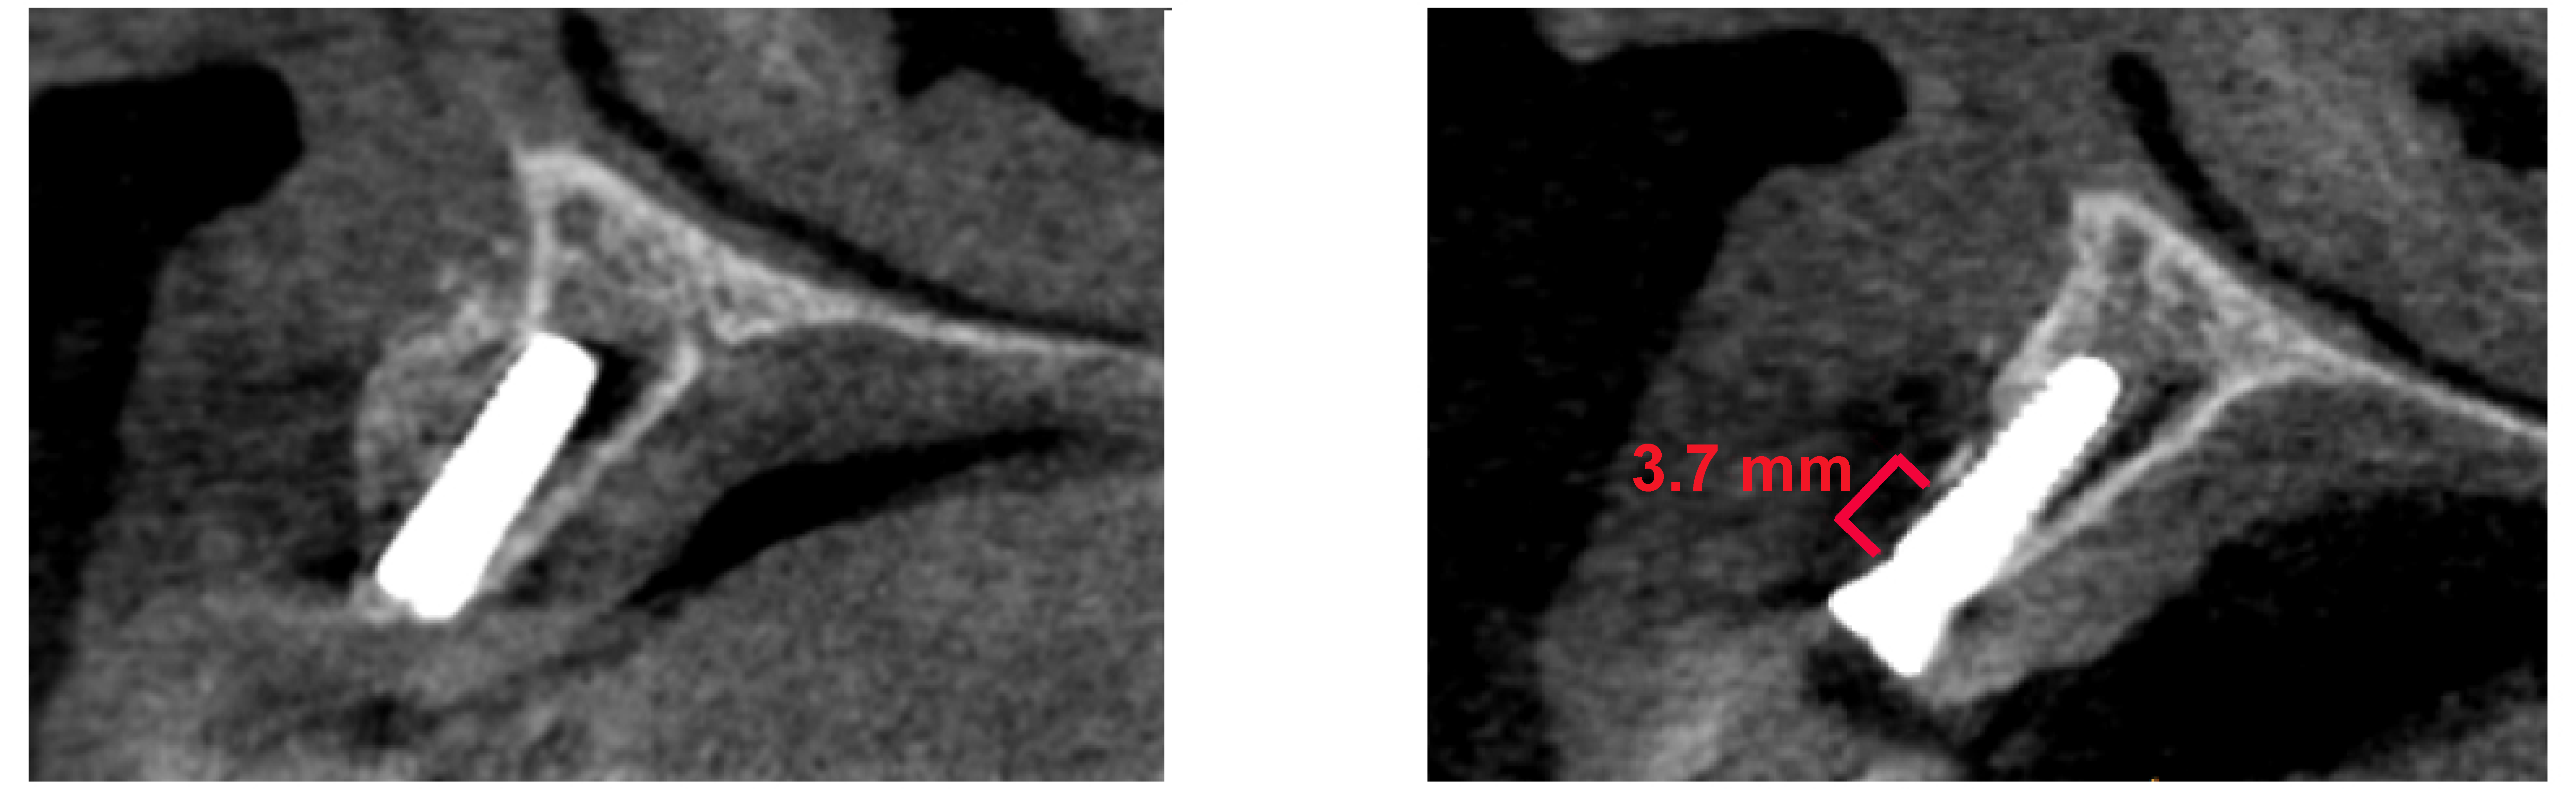

2.4. Bone Loss and Radiological Bone Measurements